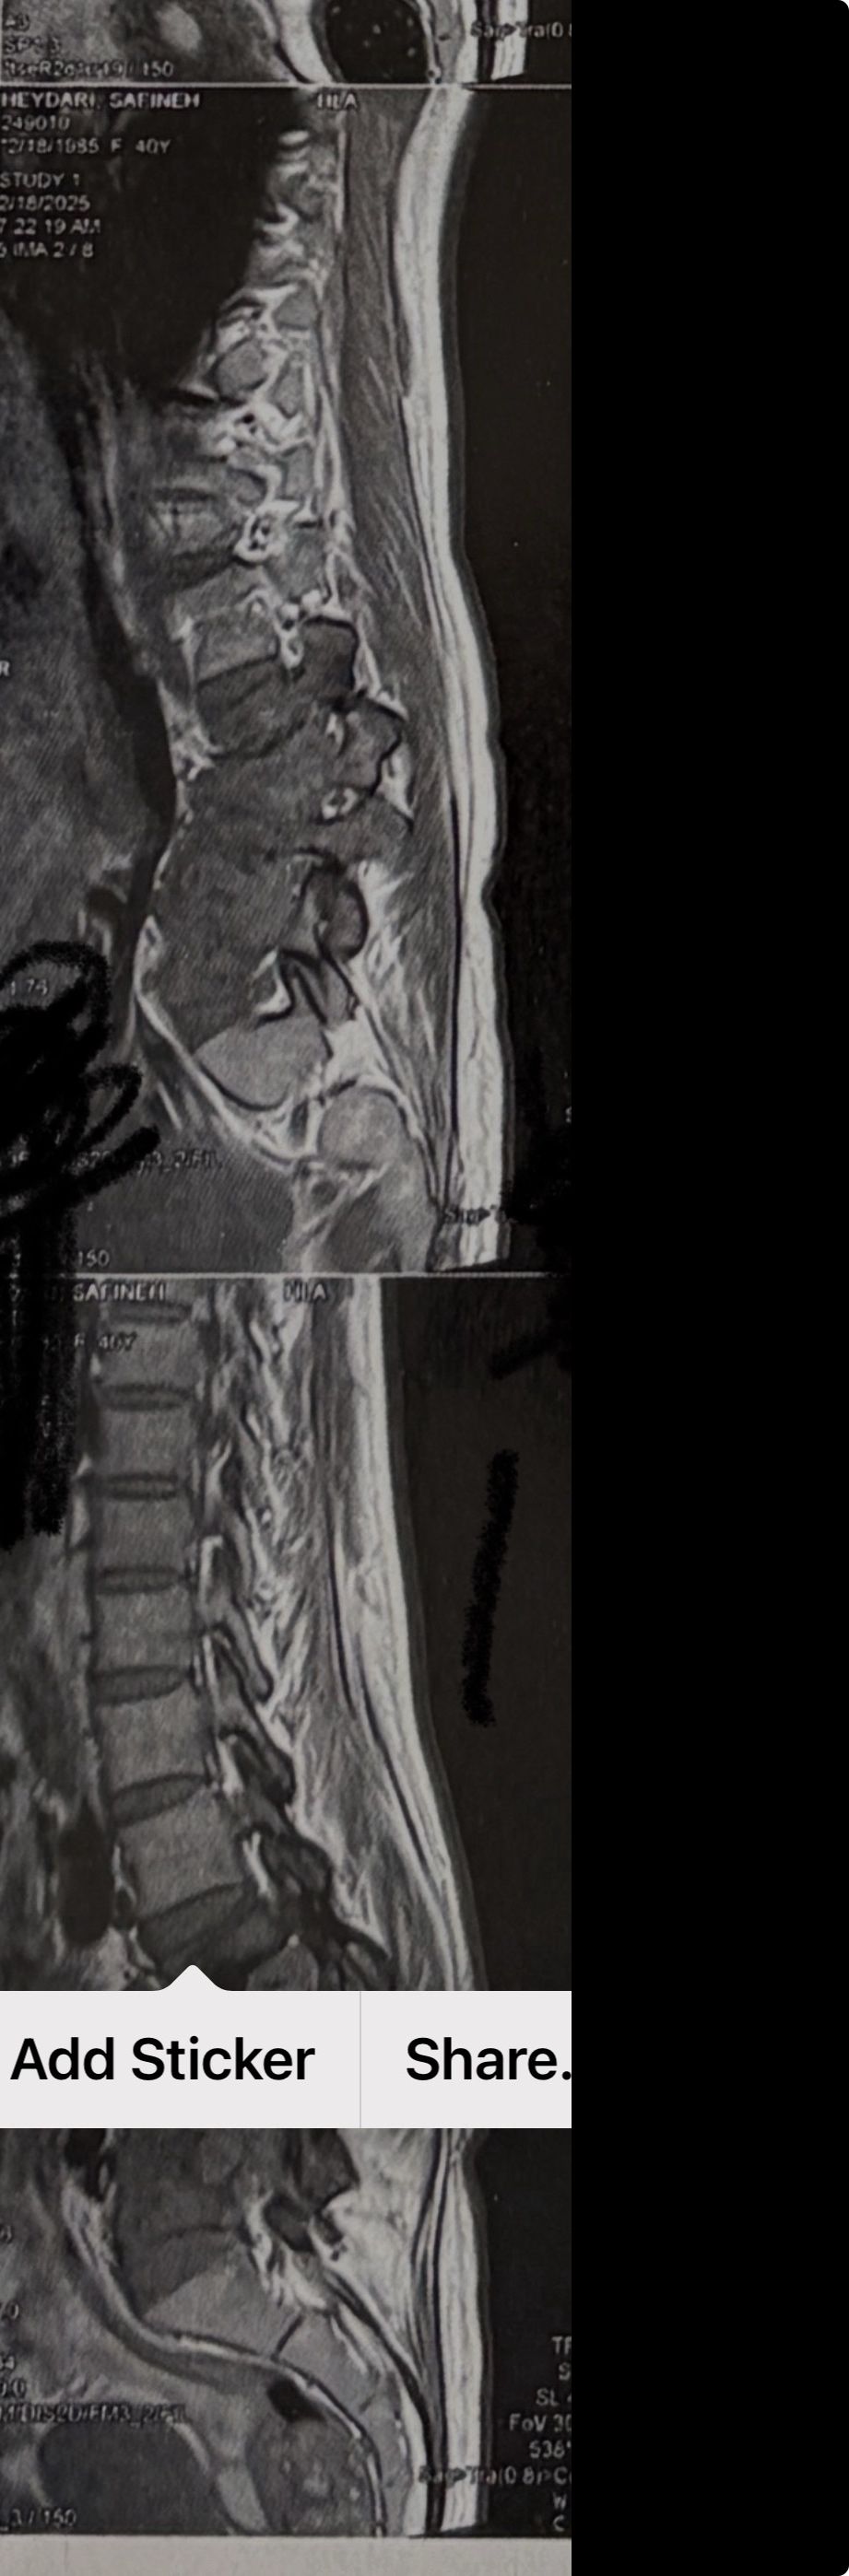

MRIs before and after proper management of this patient:

41 years old man presented to my clinic in October 2023 with acute and sever R neck pain with radicular pain to his R upper extremity along C6 dematom since 2 weeks ago. Examination didn’t show any upper motor signs. Was suggested urgent surgery

I ordered EMG/ NCV : showed mild R C6, C7 irritation without any active axonal loss

In his MRI was reported R. para R. IVF Massive extrusion. I decided to control his pain and manage this patient with reevaluation of patient every other session. For 5 sessions i just used acupuncture and laser and IFC and mild adjustments to his R. T3-T7 and mild arthosteem to above and below involved segment. Cervical adjustment considered contraindicated for this patient. From session 6th- 8th i started to use mild/gentle cervical decompression. He used soft cervical collar all the time. His pain decreased by 80 percent

I gave him cervical traction pump to be used 3-5 times per day at home for the next 3 months and i released the patient. He was evaluated every week once for one month and after that every 2 weeks. After 3 month I repeated MRI. Size of the herniated disc was reduced greater than 50 percent. Asked him to do another mri in 6 months

In general: Precise selection of the patients, examination,diagnosis, plan of management, reevaluation and treatment can be done by doctors of chiropractic for the patients with spinal disc herniation and stenosis Moreover giving reasonable time to these kind of patients under direct supervision by their chiropractic doctors can prevent unnecessary surgery. Proper selection of these kind of patients is another important fact that can be done precisely by chiropractors.